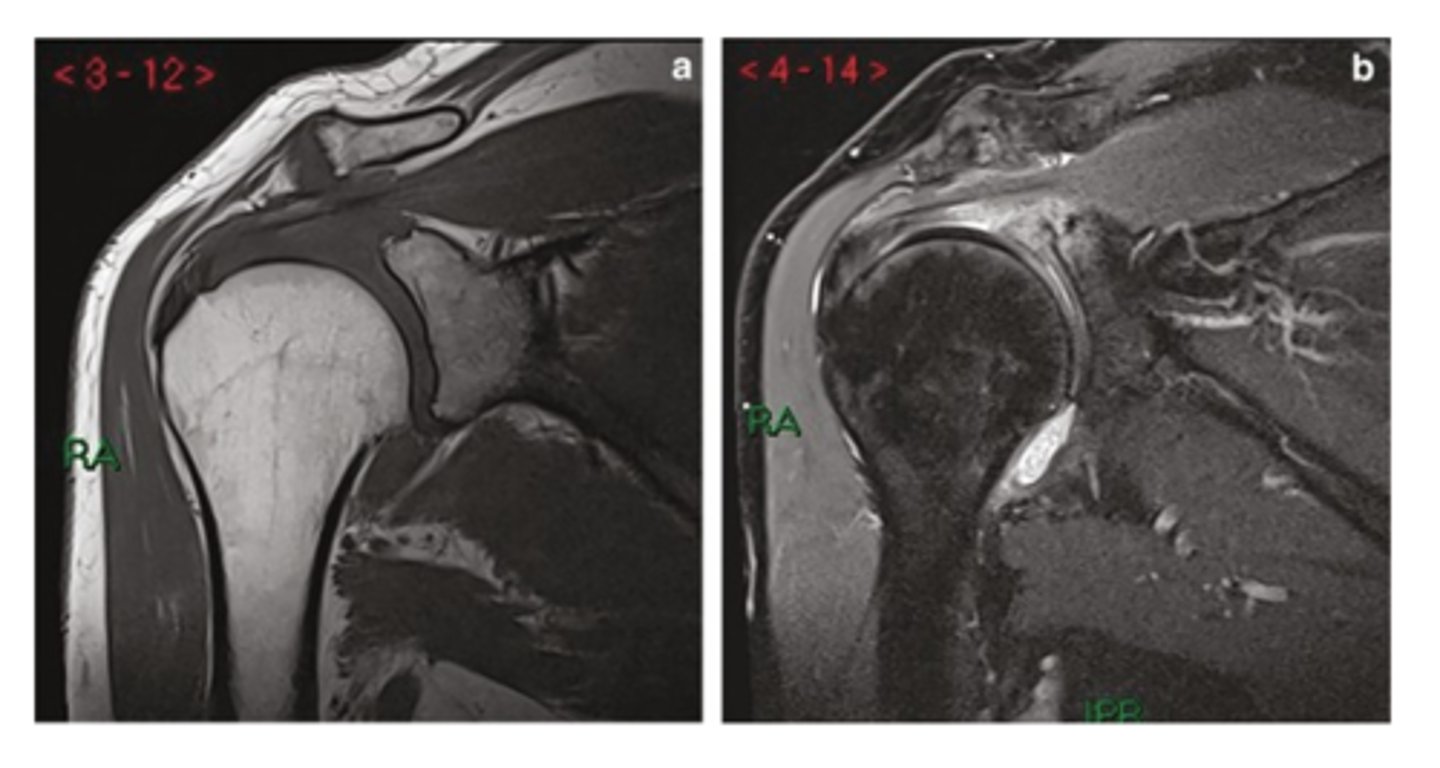

Rotator cuff tendinopathy -- image involves signal changes but the tendon is NOT yet torn

What is this image depicting w/ the rotator cuff? How do you know?

Partial tear of the rotator cuff -- focal area of disruption

Partial rotator cuff tear -- focal area of disruption

Full thickness rotator cuff tear -- 100% of the fibers are involved